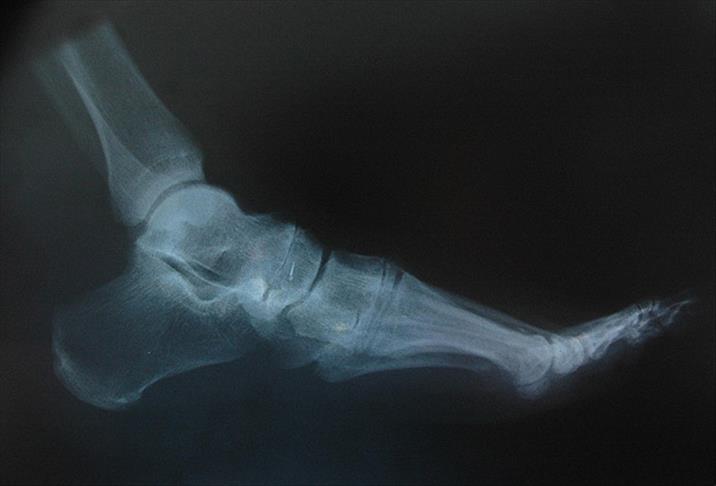

ABD'deki Tufts Üniversitesi'nde görevli bilim adamları, özel kalıplar yardımıyla tıbbı kullanıma uygun ipekten vidalar yaptı ve bu vidalar, farelerin bacaklarının arkasında kırılan noktalara yerleştirildi. İpekten vidalar, kemikleri başarılı bir şekilde bir arada tuttu ve araştırmanın sonunda da çözünmeye başladı.

İpek, sertliğinin kemiğe benzemesi ve vücutta eriyerek yok olması özelliği dolayısıyla geleneksel metal plakalar ve vidalarla karşılaştırıldığında ümit verici bir biyomühendislik malzemesi olarak kabul ediliyor.